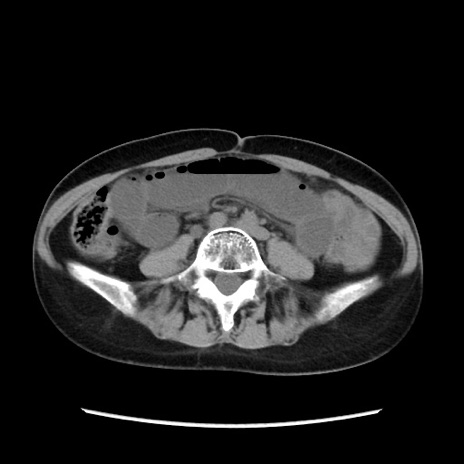

矢状断像